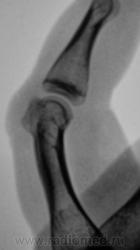

Судя по-всему тип роста экспансивный ,симпотом новообразования. Кортикальный слой как бы переходит на новообразование, контур его четкий, структура губчатая без включений, кость не вздута, окружающая ткань на мой взгляд не изменена ,окружаюшщие мягкие ткани равномерной интенсивности. Губчатая остеома?

+ за остеому

Следовательно, можно писать губчатую остеому?